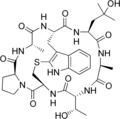

Prophalloin Phalloin

Phalloin Phallisin